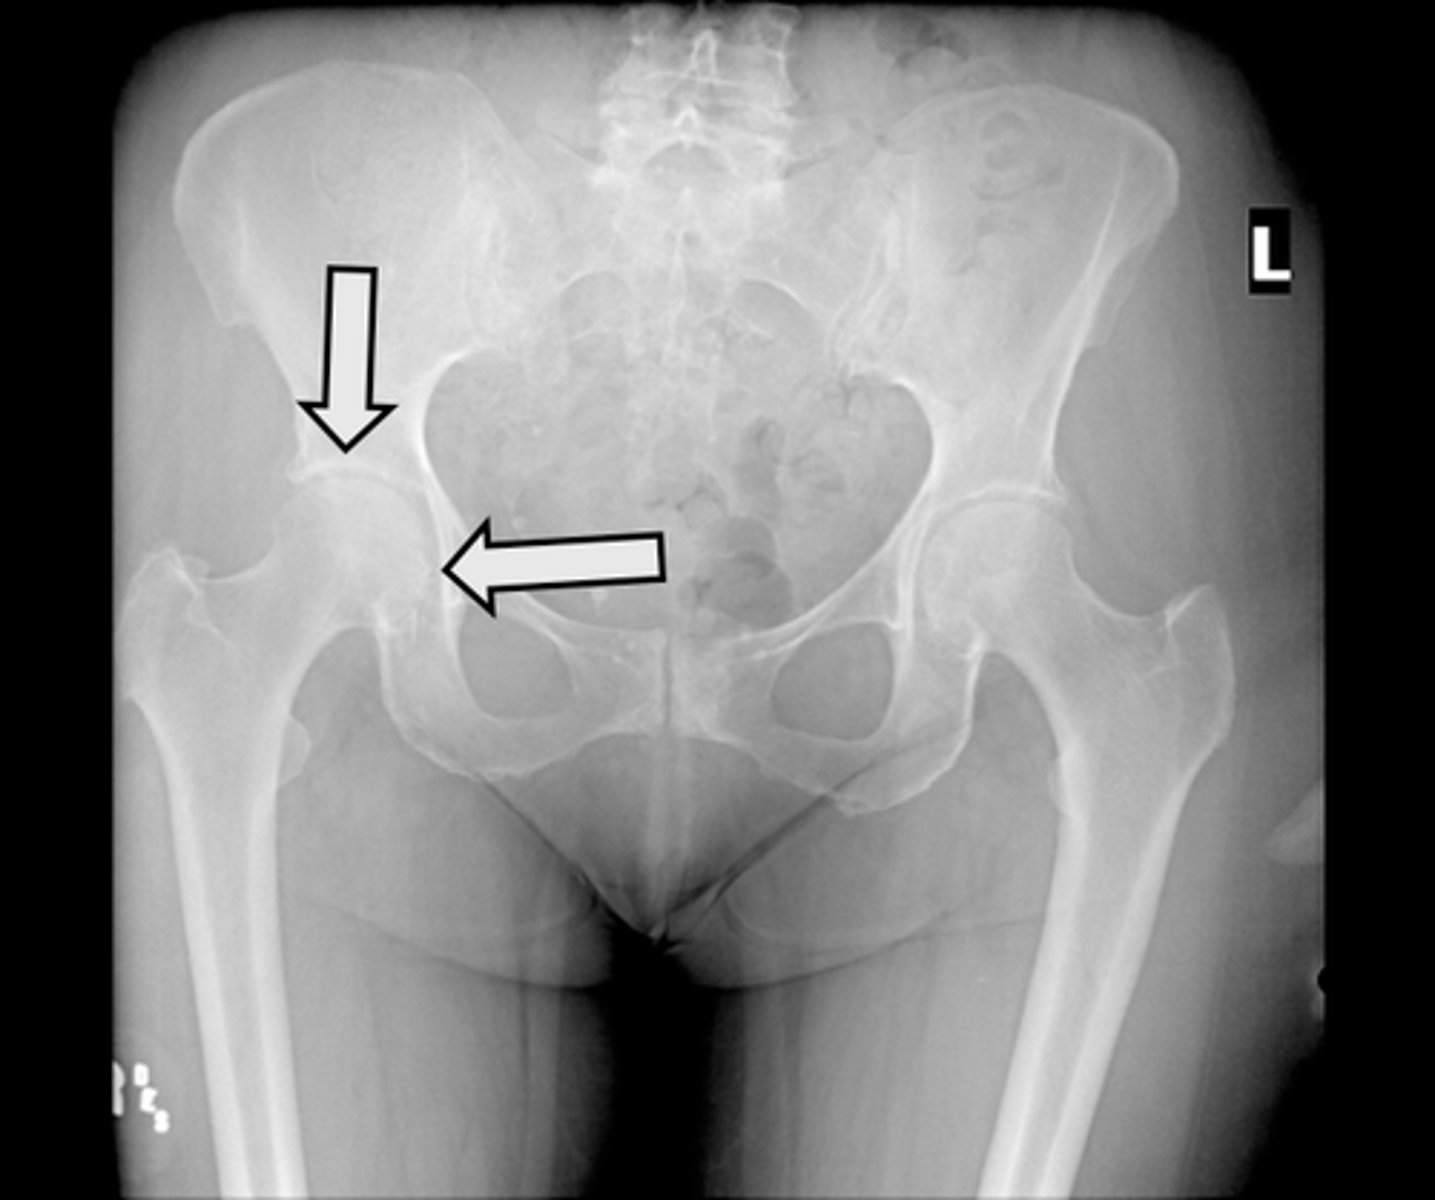

Axial bony pelvis CT

What is the image?

L ilium

What is indicated in the image?

L sacroiliac joint

R ilium

R sacroiliac joint

Sacrum

L acetabulum

L femoral head

L piriformis muscle

R femoral head

R piriformis muscle

R acetabulum (posterior part)